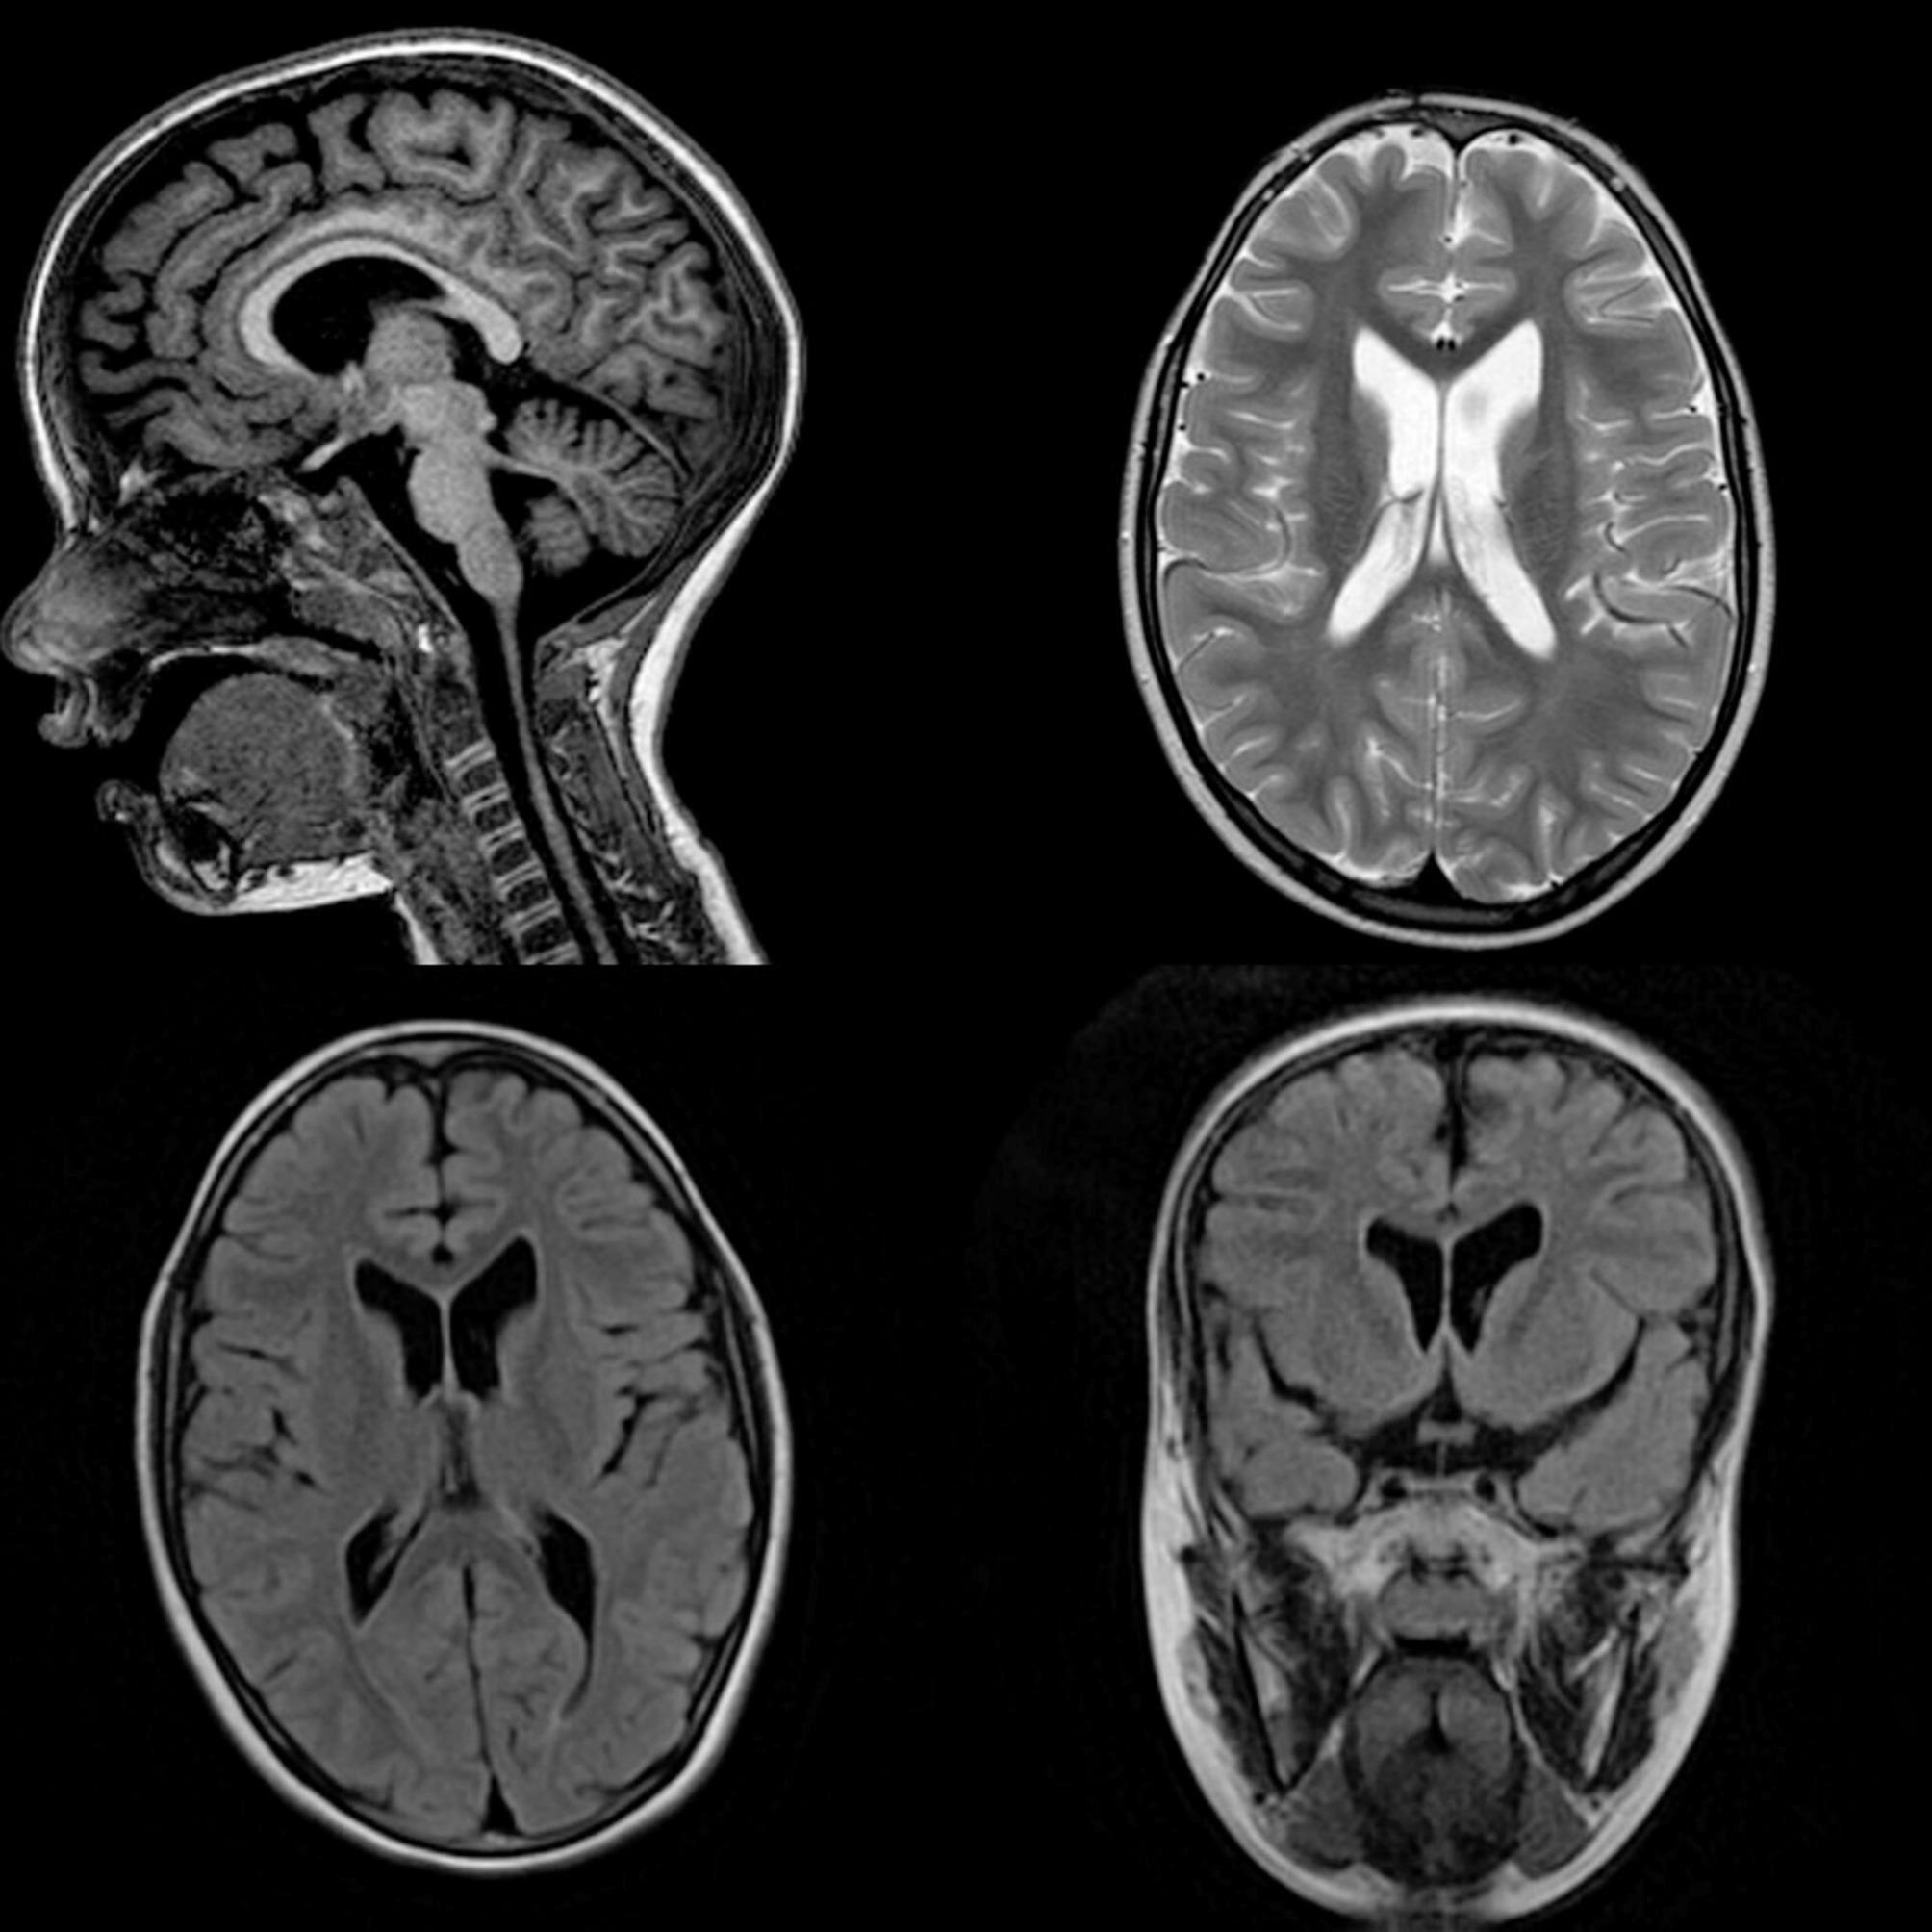

Case presentation: Our probe was born after full term pregnancy complicated by Intrauterine Growth Restriction and risk of preterm birth treated with tocolytics during the last weeks of pregnancy. On the second day of life, tremors in the lower and upper limbs were detected and lasted until the second month of life. At the age of 6 months, she was diagnosed with hypotonia. The child showed a delay in the stages of psychomotor development and a slowing of the language. Brain MRI performed at the age of 5 years revealed mild and symmetrical ectasia of the lateral ventricles, mild hypoplasia of the cerebellar vermis and brainstem with wide communication between the fourth ventricle and the cisterna magna. Neurological examination revealed dyslalia, mild generalized hypotonia, ataxic gait, motor coordination and balance deficits, while the Wechsler Intelligence Scale for Children revealed the presence of mild intellectual disability. A clinical exome and neurodevelopmental multigenic analysis revealed two variants of the POLR3A gene in compound heterozygosity (c.1795 C > A and c.1289 + 3 A > G) previously described in the literature and a novel and not yet reported CACNA2D2 variant (c.2929 C > T).

Conclusions: Beside the shared genetic and neuropsychological findings, the distinctive MRI and classical clinical signs of POLR3-related leukodystrophy have not been revealed in our case. This finding underscores the need to expand the diagnostic approach for POLR3A-related disorders, highlighting the significance of differentiating subtle clinical signs and promoting the use of genetic testing, especially in younger patients who may not yet display the typical clinical and MRI patterns. Further studies are necessary to shed light on different pathogenic mechanisms potentially responsible for the heterogeneous phenotype associated with POLR3-related disorders.